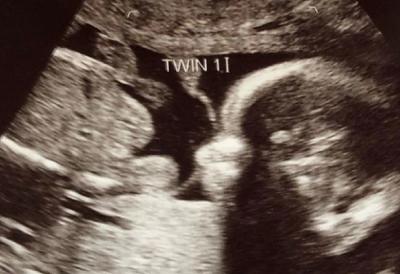

“On my first cycle on that drug we became pregnant,” she told CBS News.It wasn’t until the 12-week scan for her first baby that she was expecting two children.

Roberts had become pregnant with the twins through a phenomenon known as superfetation. It occurs when an egg is released from a woman’s ovary after she is already pregnant and implants alongside the first embryo.

Superfetation — which produces what are known as “super twins” — is very rare and there are only a few documented cases in the world, the outlets reported